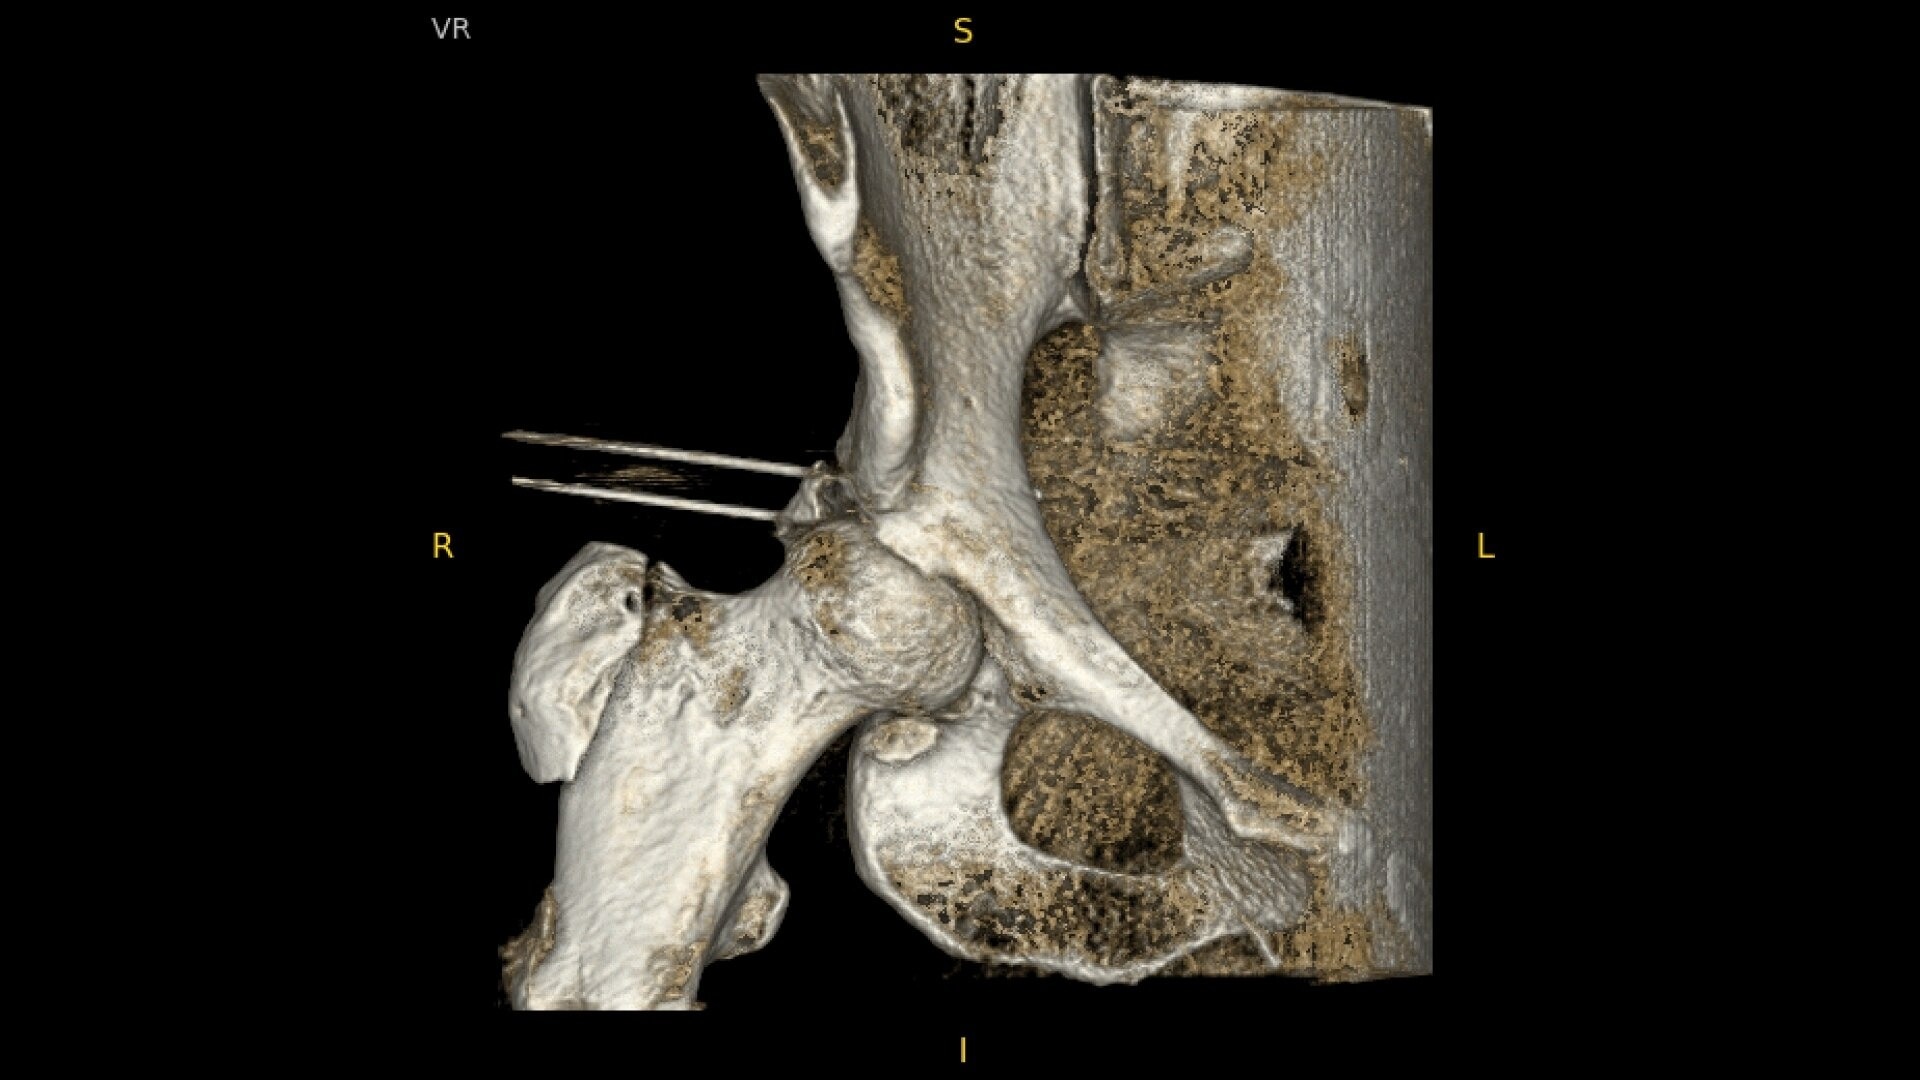

OEC C-arms provide orthopedic imaging with a large field of view optimized to clearly visualize orthopedic anatomy, such as the entire long bone femur or minute fractures in extremities. A clear display with comfortable viewing can easily show AP and lateral views, enabling efficient procedure planning.

During hip or femur imaging, capture up to 22% more Field of View by positioning detector closer to patient anatomy with the OEC low-profile X-ray tube housing compared to mono-block C-arms.

Complex orthopedic procedures require powerful imaging systems. OEC premium C-arms perform in a variety of procedures such as:

• Hip fracture fixation